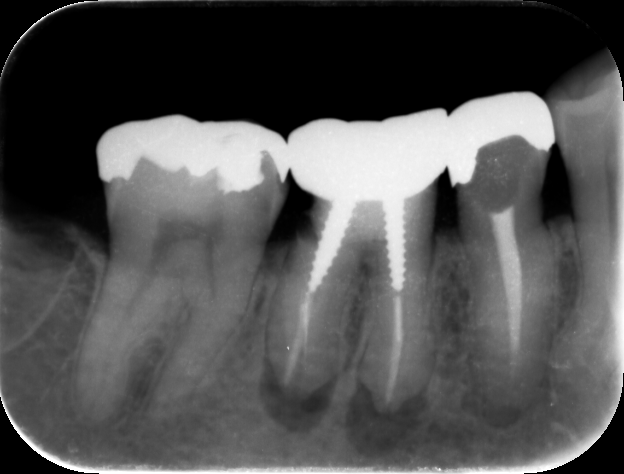

無症状の歯に対する再根管治療着手の基準は以下のとおりと考えられています。

1.根尖部エックス線透過像があり、歯冠補綴装置の再製作が必要

2.根尖部エックス線透過像が増大傾向

3.前回の歯内療法の質を高めることが可能